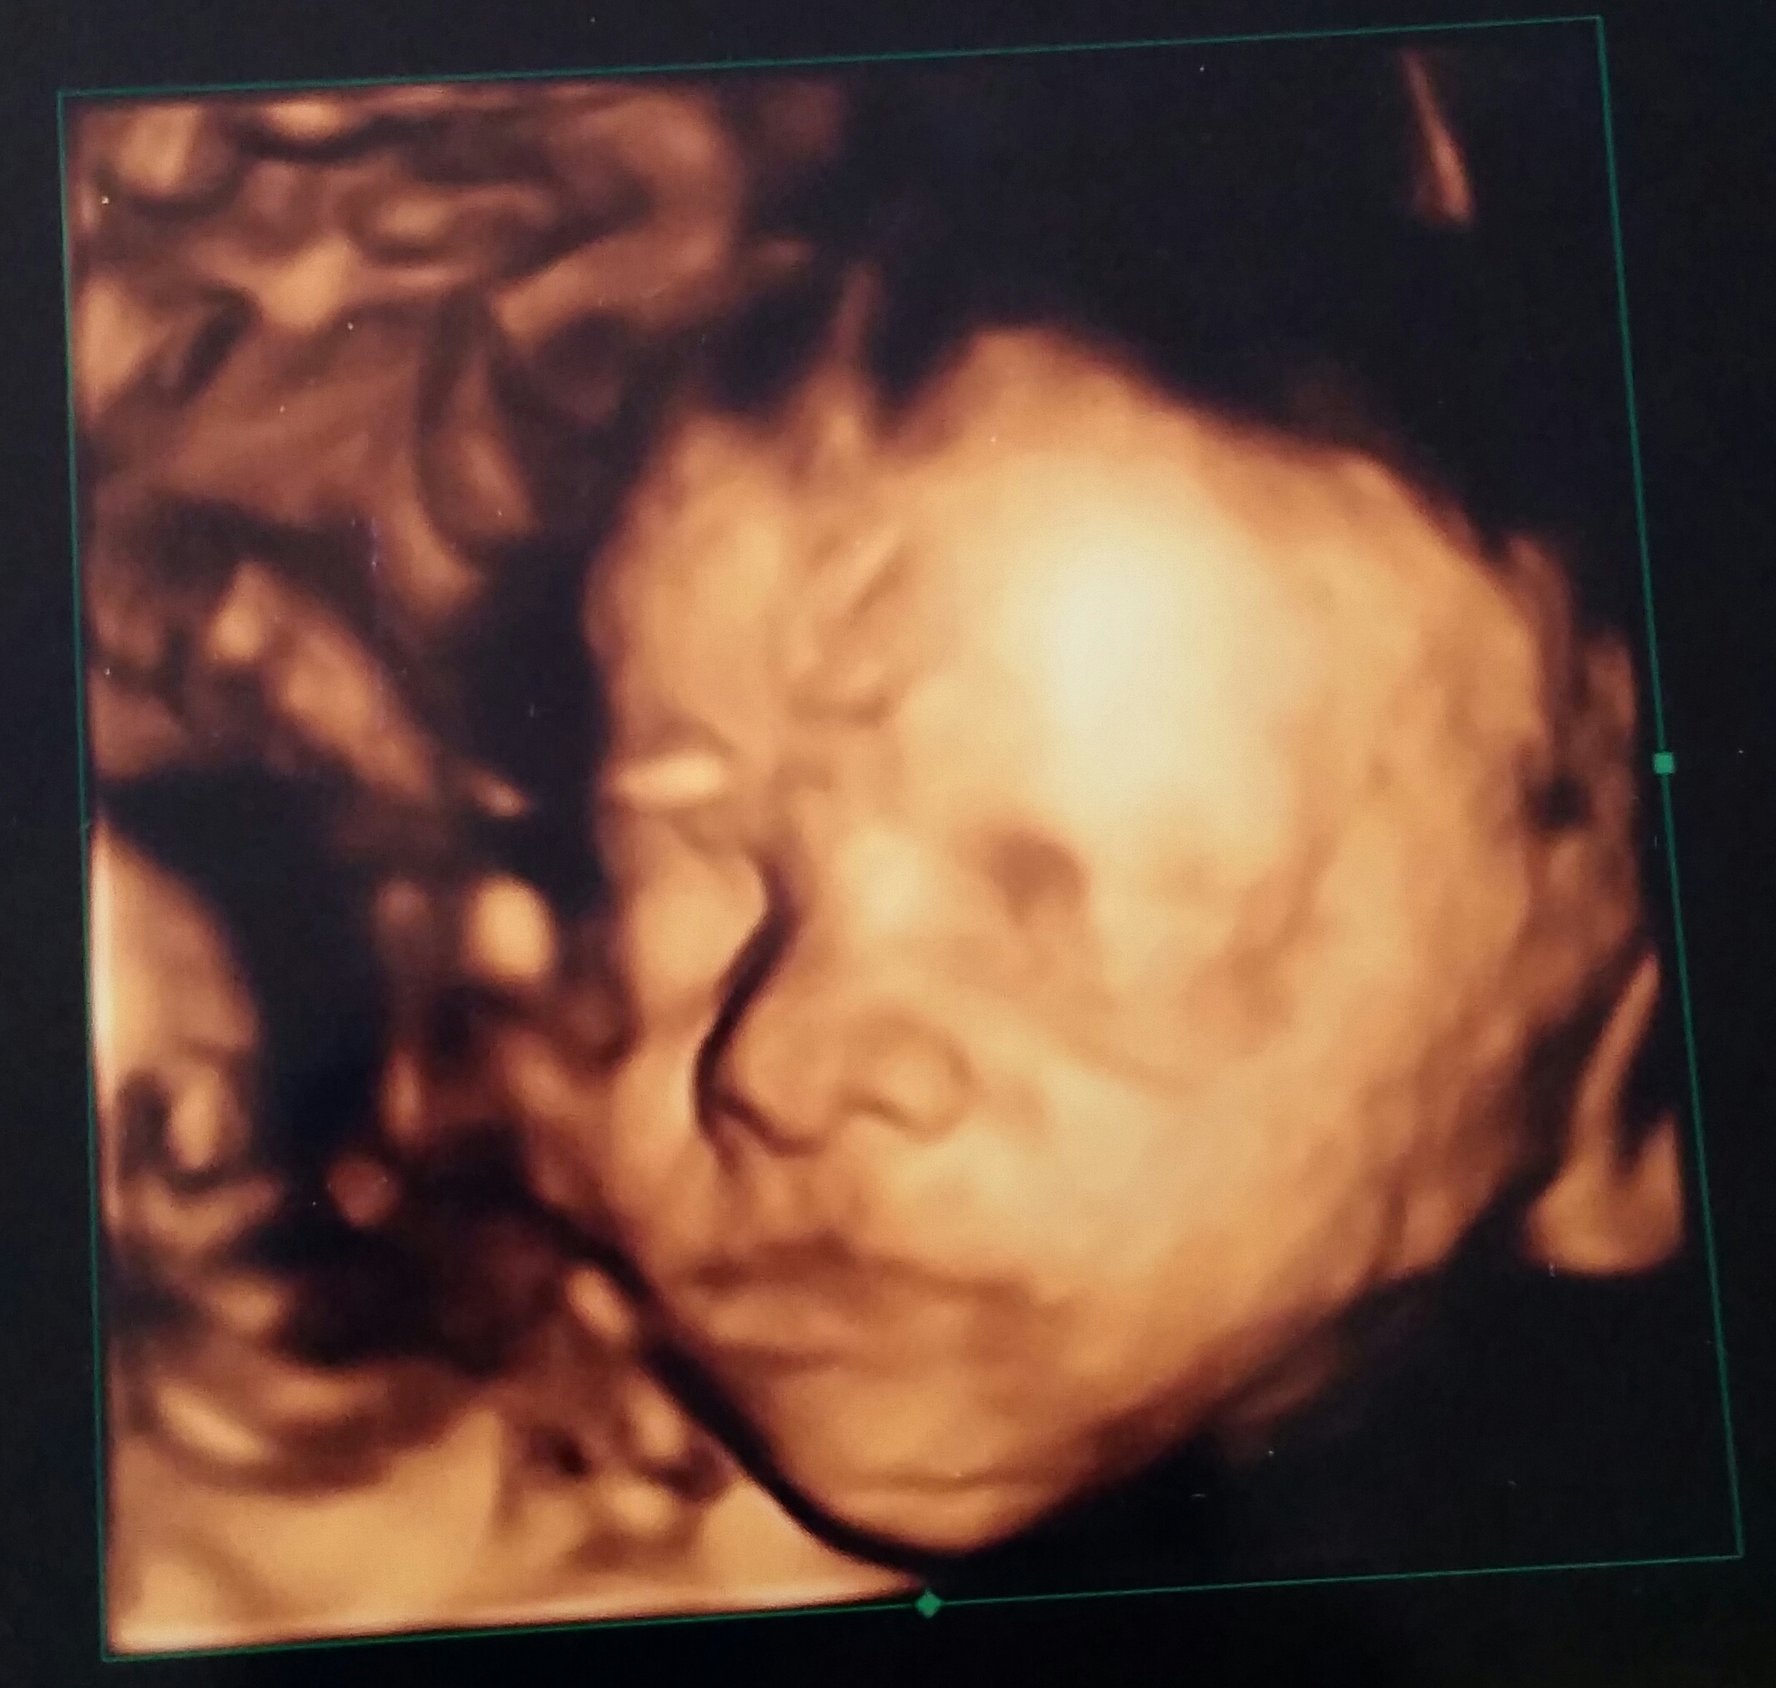

I gave his DH part of his bday present - a trip to the 3D & 4D scan and we were able to see features of our little love. She, so far, is looking more like her momma.

she looks so content, almost like she's smiling